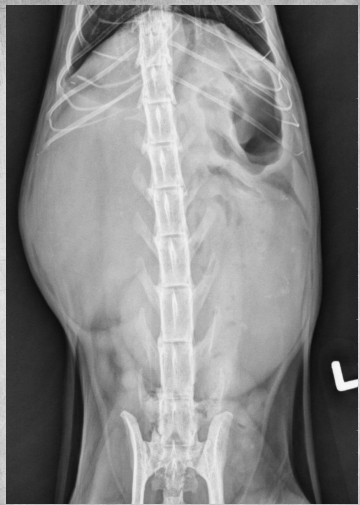

●6 yo castrated male Ragdoll

●Very thin

●Vomiting

● Liver mildly enlarged, rounded with mass effect.

● Kidneys markedly increased in size,

irregularly shaped, displaced ventrally

● Severe bilateral polycystic kidney disease

● Concurrent polycystic liver disease

soft tissue and fluid have the same density so the cysts are all homogenous with the renal tissue. you’d see the cyst pockets on ultrasound.